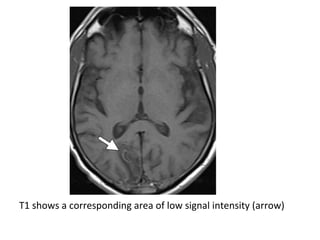

T1 shows an area of low signal intensity (arrow)

T2 shows an area of high signal intensity (arrow)

FLAIR shows an area of high signal intensity (arrow)